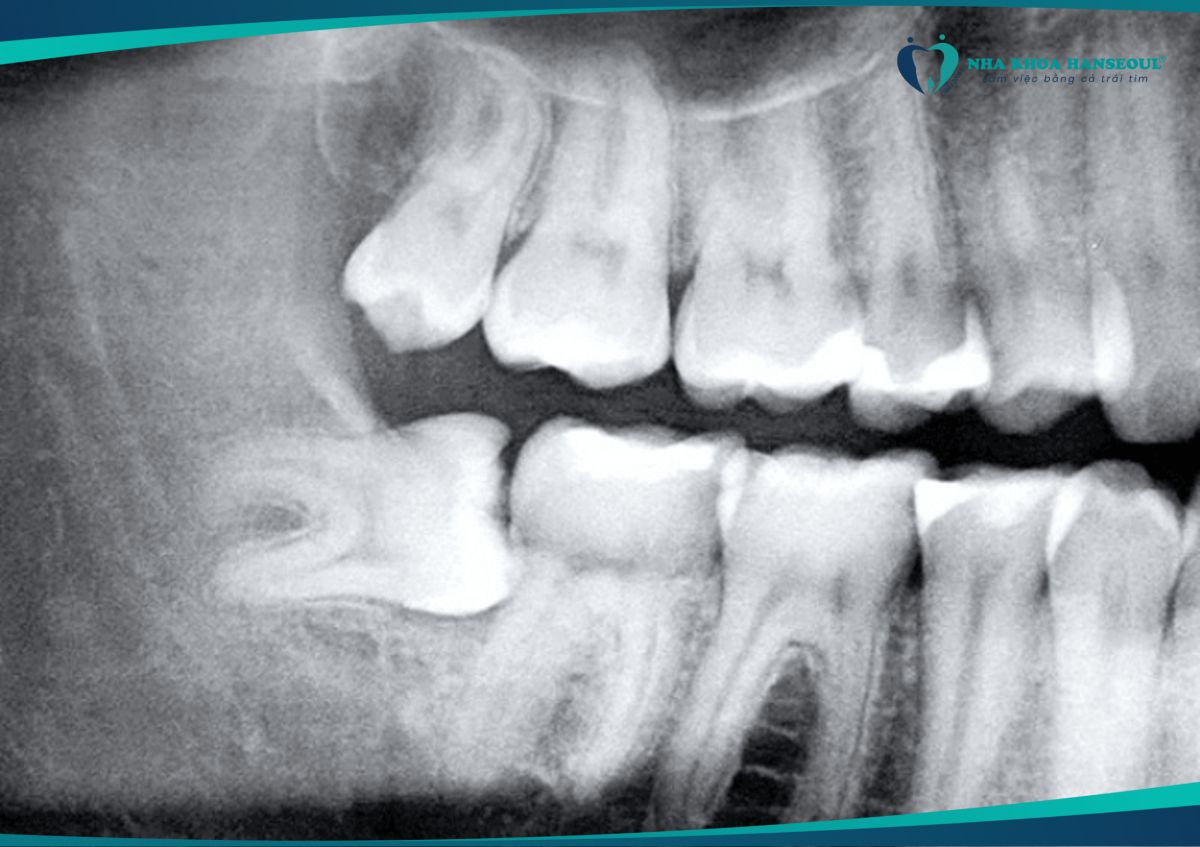

Răng mọc lệch, ngầm: Nếu chụp X-quang thấy răng khôn mọc xiên, đâm ngang hoặc nằm ngầm dưới nướu, cần nhổ sớm.

Răng khôn mọc lệch cần được nhổ để tránh gây các biến chứng nguy hiểm